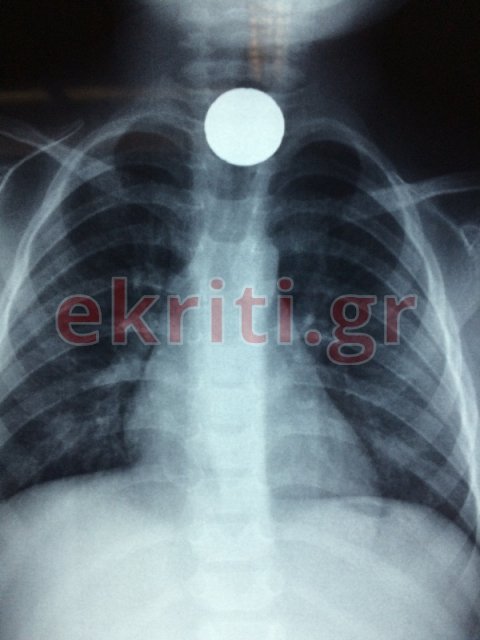

Για την ιστορία να αναφέρουμε - όπως μπορεί να δει κανείς στην αποκλειστική φωτογραφία με την ακτινογραφία που δημοσιεύει το ekriti.gr - ότι το κέρμα είχε κολλήσει στον οισοφάγο του μικρού παιδιού.

Το μικρό παιδί, άγνωστο πως κατάπιε το μικρό αντικείμενο (ένα κέρμα 20λεπτο), με τους γονείς του να το μεταφέρουν άμεσα στο Βενιζέλειο νοσοκομείο Ηρακλείου που εφημέρευε. Αφού έγιναν όλες οι απαραίτητες εξετάσεις, αποφασίστηκε να μπει στο χειρουργείο.